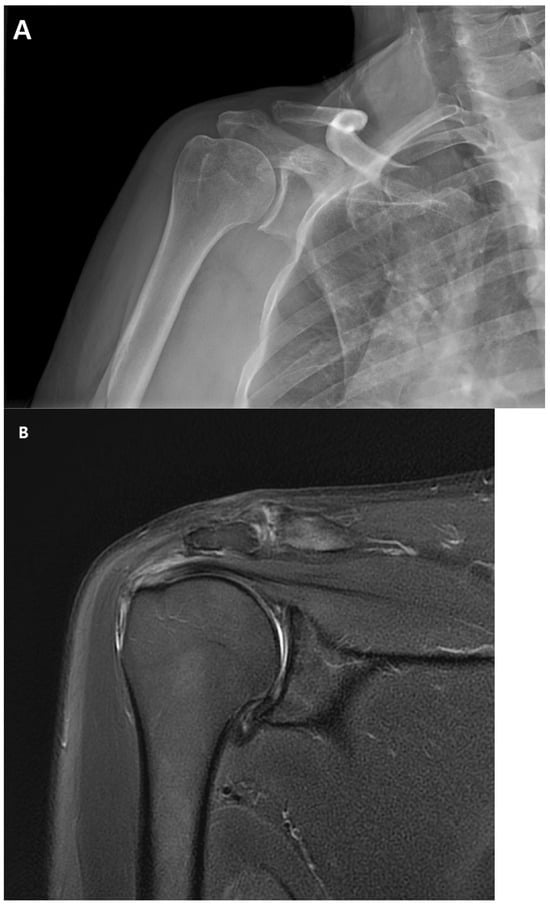

Figure 1.

(A). Preoperative plain anteroposterior radiograph. Acromioclavicular joint alignment was acceptable with no arthritic changes. The glenohumeral joint showed adequate joint space and congruency. (B). Oblique coronal T2 fat-suppressed magnetic resonance imaging (MRI). MRI of the right shoulder showed a thickened axillary pouch with normal hypointense joint capsule. The supraspinatus tendon had high signal variation with intact continuity.